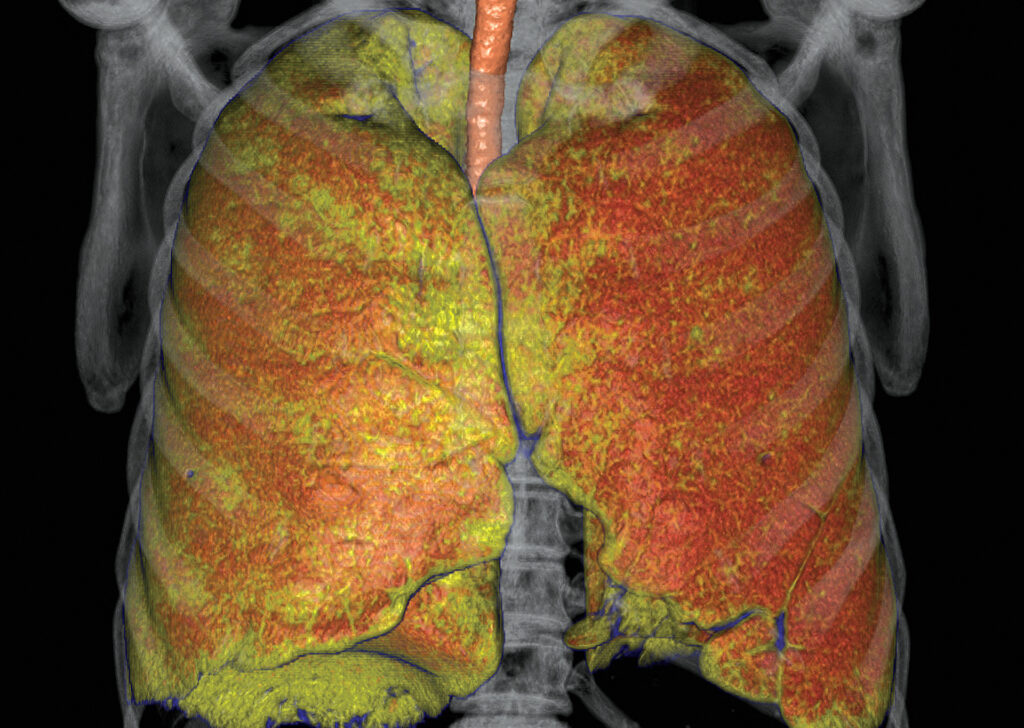

CT Lung Density Analysis

CT Lung Density Analysis software provides CT values for pulmonary tissue from CT thoracic datasets.